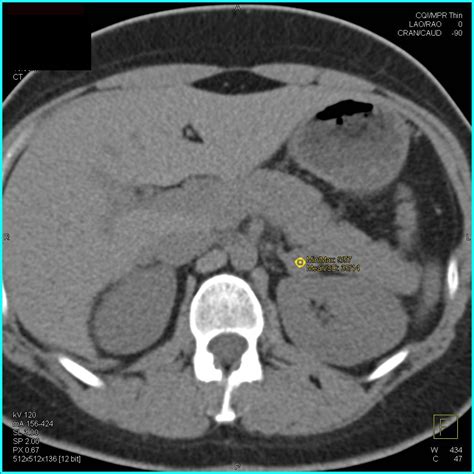

• Imaging tests: Computed tomography (CT) scans and magnetic resonance imaging (MRI) are commonly used to detect adrenal adenomas. These tests provide detailed images of the adrenal glands and can help determine the size and location of the tumor.